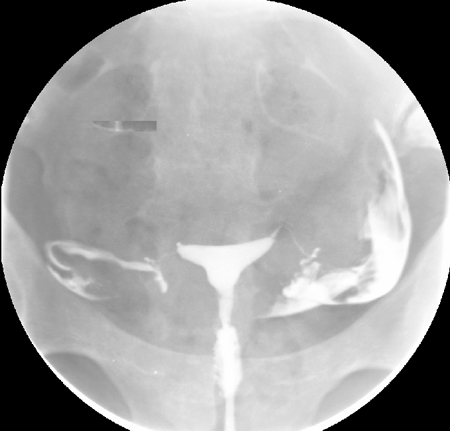

Saline infusion ultrasound with polyp

From the collection of Dr Jared C. Robins